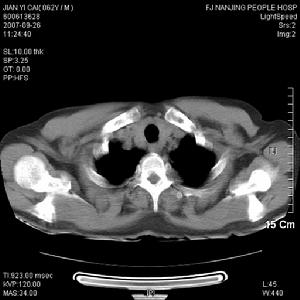

2、影像學表現

二、X線上,病灶的密度常有差異,取決於病理成分,病灶如主要為纖維組織常表現為囊狀透光區;如主要為砂礫樣鈣化新生骨者常呈磨砂玻璃狀;如新生骨鈣化較多時則表現為一片明顯的增白區。每一病灶,可以上述表現按不同比例組合出現。

骨纖維異常增殖症①變形性骨炎型:常為多骨型病變表現,其特點是顱骨增厚,顱骨外板和頂骨呈單側泡狀膨大,骨內板向板障和顱腔膨入,增厚的顱骨中常見局限和瀰漫的射線透明區和濃密區並存,這種骨吸收與硬化並存極似Paget變形性骨炎的表現。顱骨擴大和硬化,可從額骨擴大到枕骨。面部受累可導致眶和鼻腔狹窄及鼻竇腔消失,此型約占56%。②硬化型:此型多見上頜肥厚,可致牙齒排列不整,鼻腔、鼻竇受壓變小。上頜骨受累多於下頜骨,且多為單骨型。損害呈硬化或毛玻璃樣外觀。相反,下頜骨損害多見於多骨型,表現為孤立的骨壁光滑且可透過射線。此型約占23%。③囊型:顱骨呈孤立或多發的環形或玫瑰花形缺損,缺損從菲薄的硬化緣開始,其直徑可達數厘米。孤立的損害有似嗜酸性肉芽腫,多發的缺損可誤認為HandSchüllerChristian病,偶有數種X線類型出現於同一個體上。此型約占21%。套用CT或MRI檢查,能明確病變的位置和範圍,且能顯示與軟組織的聯繫。定期檢查可動態觀察病變的發展程度,對選擇術式進路、減少併發症和估計預後甚為重要。